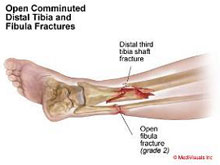

Fracturas de tibia y peroné

La región de la pierna engloba las diáfisis o zonas centrales de la tibia y el peroné. Son las fracturas de huesos largos (fémur, tibia, húmero, cúbito y radio) más frecuentes en el adulto y pueden producirse por un impacto directo (accidentes de tráfico, caídas desde gran altura, deportes de contacto o de motor) o por un mecanismo indirecto (torsión de la pierna en deportes de salto o sobrecarga repetida en bailarines y reclutas). El tratamiento varía en función del desplazamiento y el grado de afectación de la musculatura y piel circundante. El avance en las técnicas quirúrgicas ha permitido, cuando la indicación lo requiere, el empleo de una cirugía mínimamente invasiva que permite reparar grandes fracturas a través de mínimas heridas disminuyendo la agresión al tejido y favoreciendo la rápida incorporación a la actividad diaria.